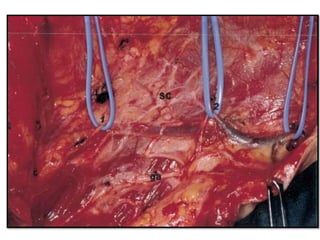

• #84 Boundaries of a complete functional neck dissection on the right side of the neck. ML, midline; BM, inferior border of the mandible; C, clavicle; TM, trapezius muscle; ga, great auricular nerve; SC, sternocleidomastoid muscle; sm, strap muscles; pm, platysma muscle; ej, external jugular vein; aj, anterior jugular vein; SG, submandibular gland.

• #103 The fascia of the sternocleidomastoid muscle is dissected medially. The external jugular vein is included in the fascia (right side). ej, external jugular vein; F, fascia; SC, sternocleidomastoid muscle. Fascial retraction should be done with extreme care because the thin superficial layer of the cervical fascia. is the only tissue now included in the specimen.

• #104 Lateral retraction of the sternocleidomastoid muscle allows the dissection of the medial surface of the muscle. The dissected fascia is carefully pulled medially (right side). IJ, internal jugular vein shinning through the fascia; SC, sternocleidomastoid muscle; F, dissected fascia; tm, trapezius muscle; SG, submandibular gland.